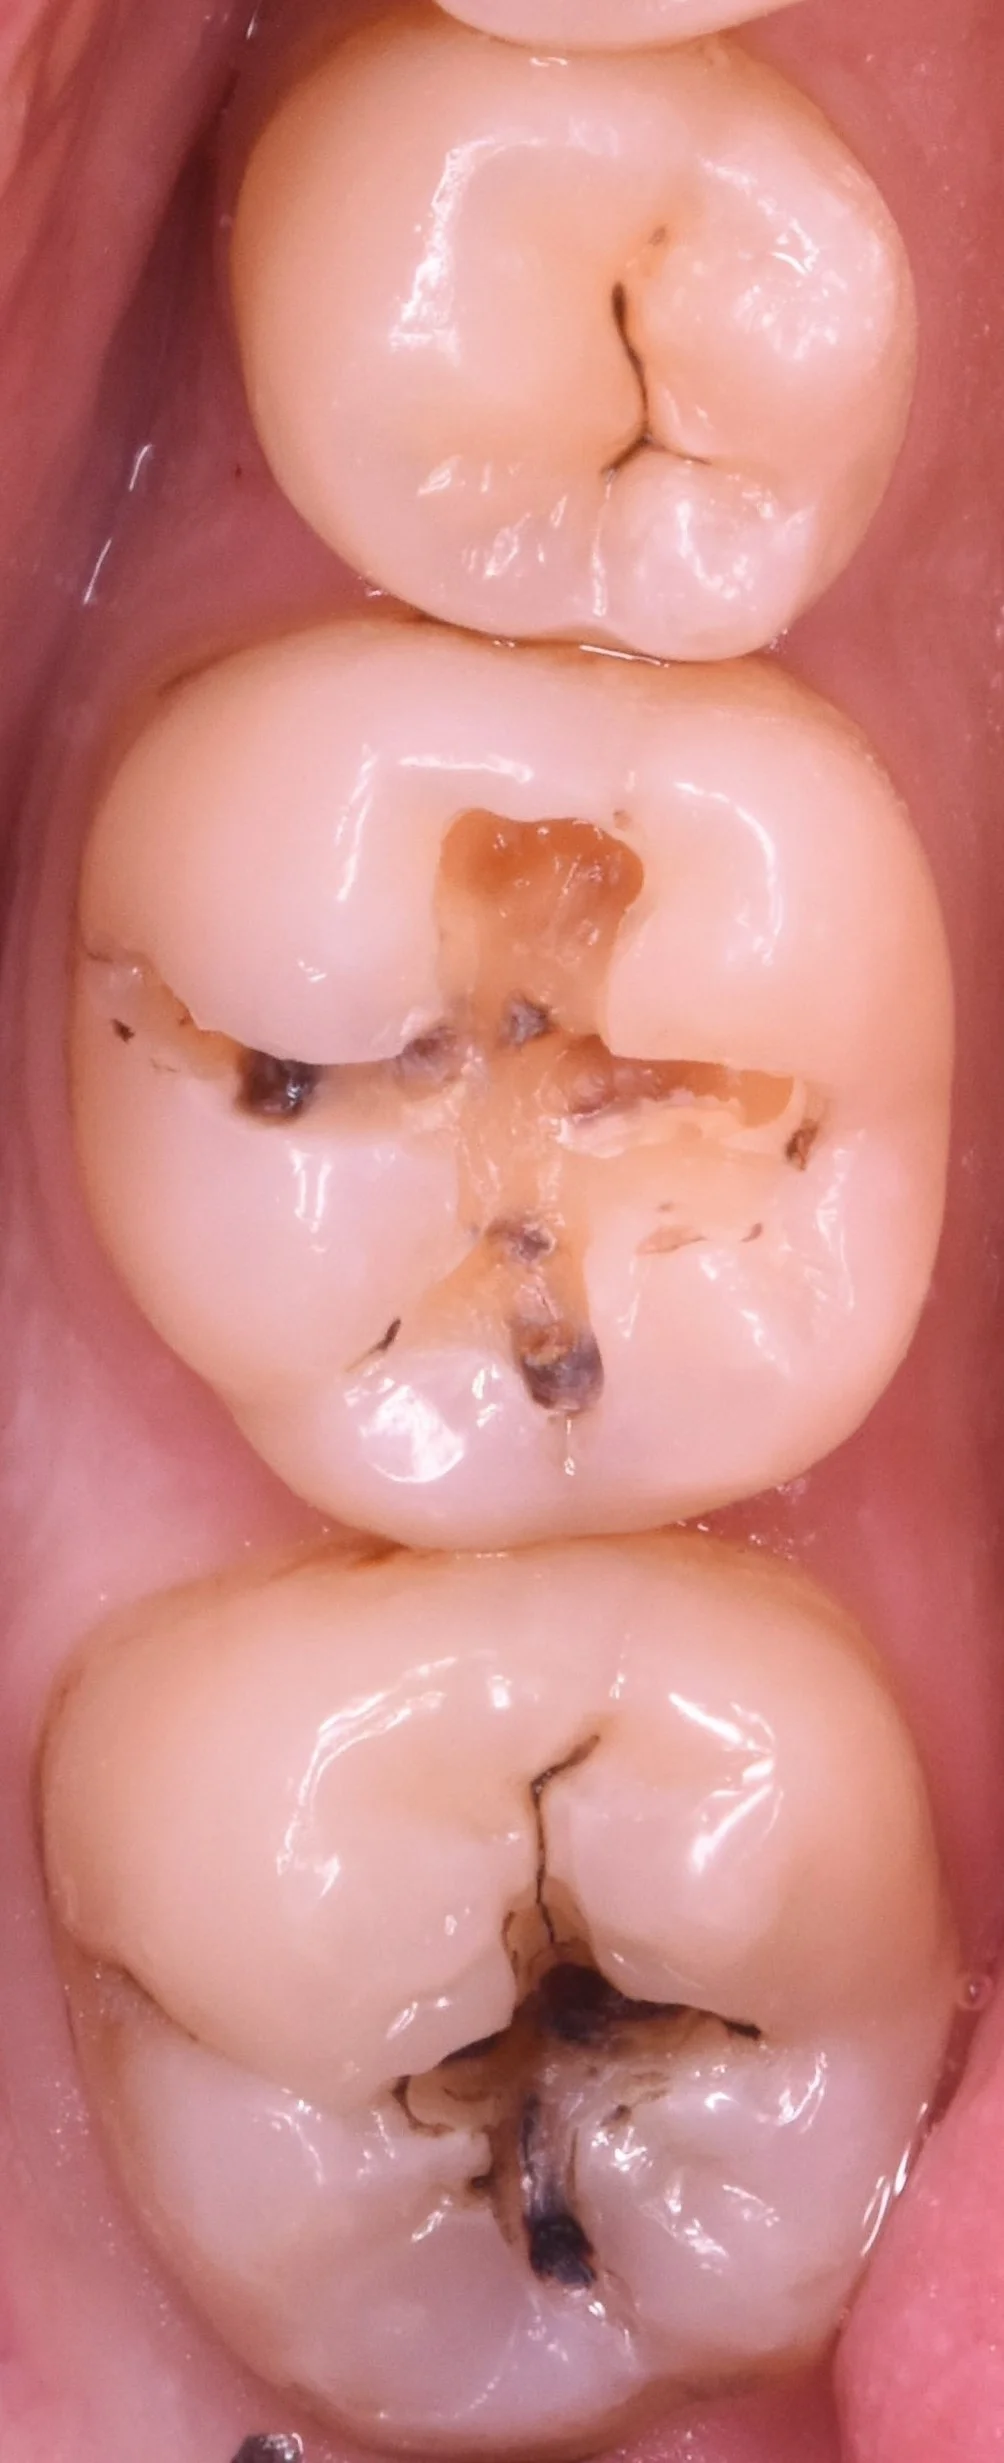

では術前の写真からです。

画像内左側の2本が今回手を付ける部位になります。

金属の詰め物・白い詰め物がそれぞれ入っていますが、黒い部分がすでに目立っていますね。

形を見る限り、それぞれの詰め物がかけた場所から内面に虫歯が入り込んでしまったようです。